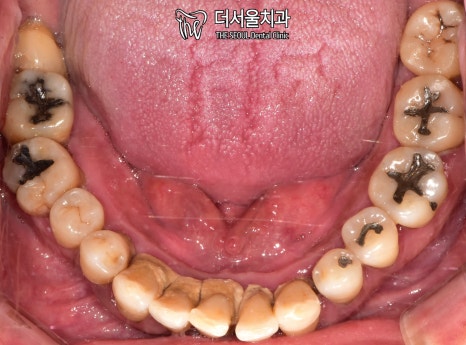

교합면을 확인했을 때도 마찬가집니다.

인접면에 있는 충치와

누워있는 사랑니까지 찾아볼 수 있었습니다.

단기간 내에 끝낼 수 없는 케이스죠.